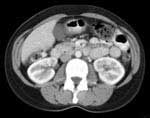

An example of what your scan will look like.